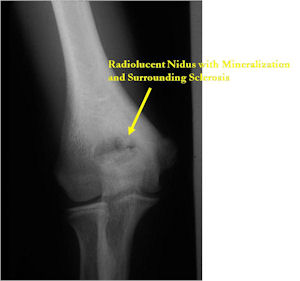

Plain X-Rays:

- Lucent nidus surrounded by a zone of marked sclerosis

- The nidus may demonstrate mineralization/ossification usually from the center outward that appears as a central zone of density within the nidus

- A nidus that is heavily ossified may blend in with the surrounding sclerosis and be difficult to detect on a plain x-ray.

- Periosteal bone is solid, rarely lamellated

- Cortical and subperiosteal osteoid osteomas are usually associated with much more reactive sclerosis than medullary tumors

- The periosteal reaction is continuous and often appears as cortical thickening (benign appearing reaction)